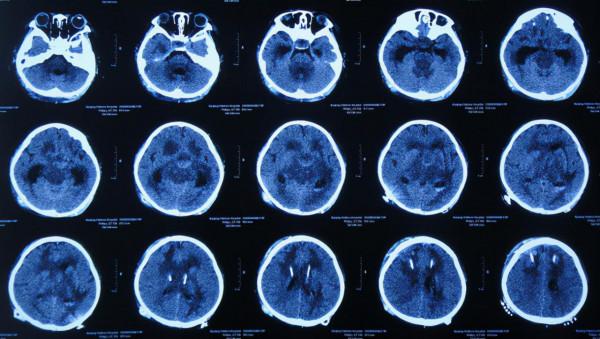

入院當天頭部CT示右側顳角擴張,腦室內有3根管(圖-33)。

圖-33:2020年5月19日頭部CT

入院後第3天即2020年5月21日,拔除了原腦室引流管和Ommaya囊+左側腦室外引流術和右側顳角引流術(圖-34)。

圖-34:2020年5月21日頭部CT